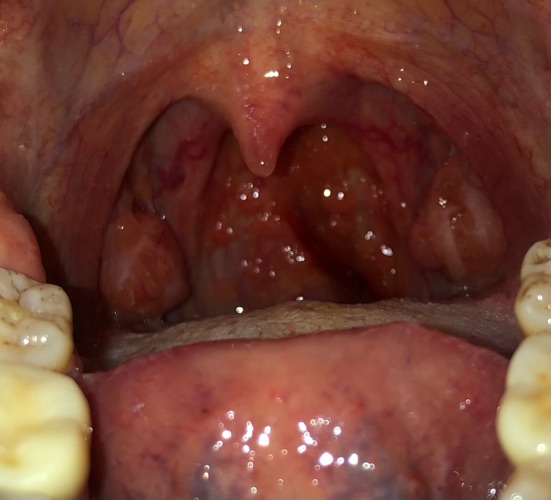

Bs thấy 2 amygdal em to; sung huyết. Tuy nhiên việc khạc ho ra dây máu có khá nhiều nguyên nhân như nguyên nhân tổn thương ở hầu họng; nguyên nhân ở phổi; nguyên nhân đường dẫn khí; ... Bs cần hỏi em thêm một số triệu chứng nữa để tư vấn cẩn thận cho em rồi kê đơn. Nếu em có thời gian em đặt lịch khám bs để trao đổi cụ thể nhé